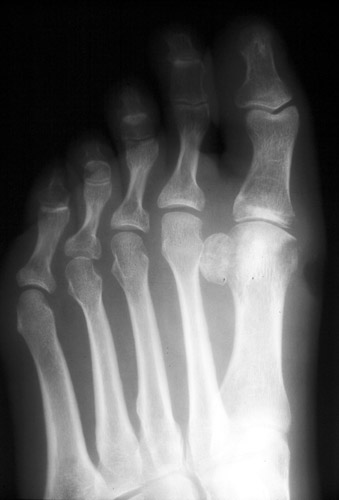

Gout

images/LARGE/72goutMRcor.JPG

images/LARGE/71goutMRsag.JPG

images/LARGE/73goutMRaxt2.JPG

images/LARGE/74goutMRaxpd.JPG